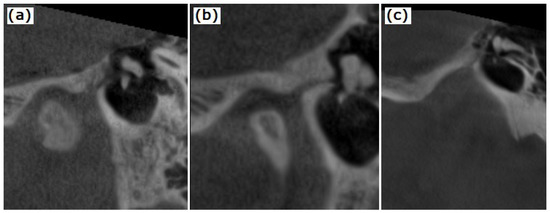

2.2. CBCT Examination of the TMJ and the Temporal Bone